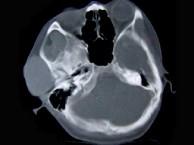

问题 女性,19岁,右侧面颊部肿胀1年,CT检查如图所示,请选择最佳答案()

选项 A.右颊部神经纤维瘤 B.右颊部血管瘤 C.右颊部脂肪瘤 D.右颊部横纹肌肉瘤 E.右颊部血肿

答案 B